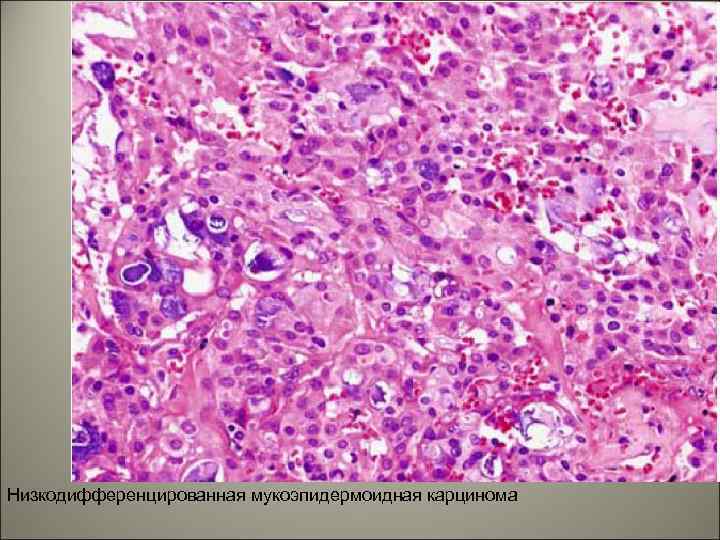

• В группу низкодифференцированных отнесены те мукоэпидермоидные карциномы, в которых выражен клеточный полиморфизм, имеются патологические митозы, резкий гиалиноз стромы единичные мелкие кисты. Клеточный состав представлен промежуточными и эпидермоидными элементами. Метастазирует опухоль, в основном лимфогенно.

Низкодифференцированная мукоэпидермоидная карцинома